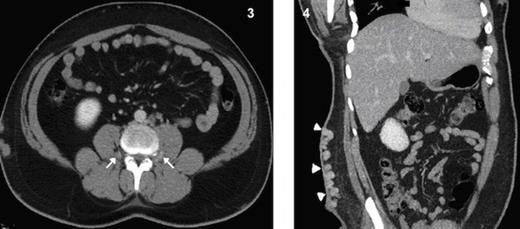

Dilated and tortuous azygous & hemiazygous veins (Fig. 2), with multiple prevertebral and paravertebral collaterals (Fig. 3) as well as superificial collateral veins in the abdominal wall (Fig. 4) were seen. Left renal vein is draining into the hypoplastic segment of IVC (Fig. 5).

Coronal MPR CT image shows grossly dilated azygous vein (arrow) and hemiazygous vein (arrow heads)